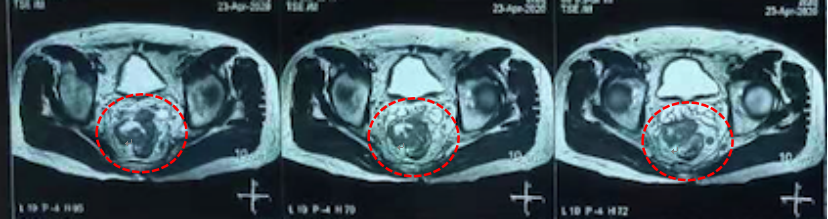

(2)2020-4-25 盆腔增强MRI:直肠中上段占位,考虑肿瘤性病变,累及肠系膜筋膜及腹膜反折,直肠周围系膜、双侧盆壁及双侧腹股沟区多发淋巴结,部分淋巴结转移可能。